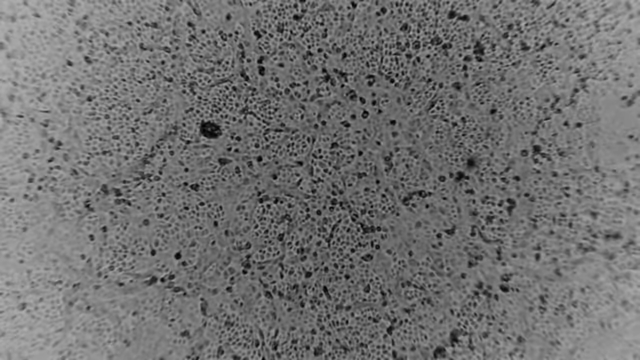

![[서울=뉴시스]호주 멜버른 소재 피터 도허티 면역·감염 연구소가 29일 성명을 내고 "과학자들이 환자 샘플로부터 우한 코로나바이러스를 성공적으로 배양했다"고 밝혔다. (사진출처=피터도허티연구소 홈페이지 캡처) 2020.01.29.](https://img1.newsis.com/2020/01/29/NISI20200129_0000469292_web.jpg?rnd=20200129152514)

[서울=뉴시스]호주 멜버른 소재 피터 도허티 면역·감염 연구소가 29일 성명을 내고 "과학자들이 환자 샘플로부터 우한 코로나바이러스를 성공적으로 배양했다"고 밝혔다. (사진출처=피터도허티연구소 홈페이지 캡처) 2020.01.29.